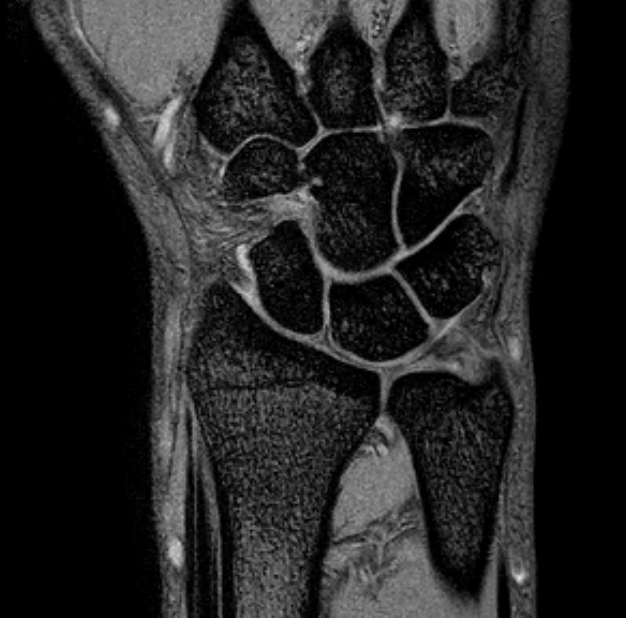

- 主体会病院のMRIがPhilips社の3T-MRIに新しく更新されました。特徴は高磁場により信号が強く、高分解能の画像がとれる事です。特に、手関節の様な小さな部位がきれいに撮影出来ます。頭部では細い

脳神経もきれいに描出出来ます。また、心臓も撮影出来るようにしました。今までの検査で検出できない小さな

無症候性心筋梗塞もMRIでは明瞭に描出出来る様になりました。肺野以外は、MRIの画像診断に果たす役割は非常に大きく、MRI無しでは診断出来ない時代になりました。今後、皆様の診療に役立つよう、努力するよう努めてまいります。